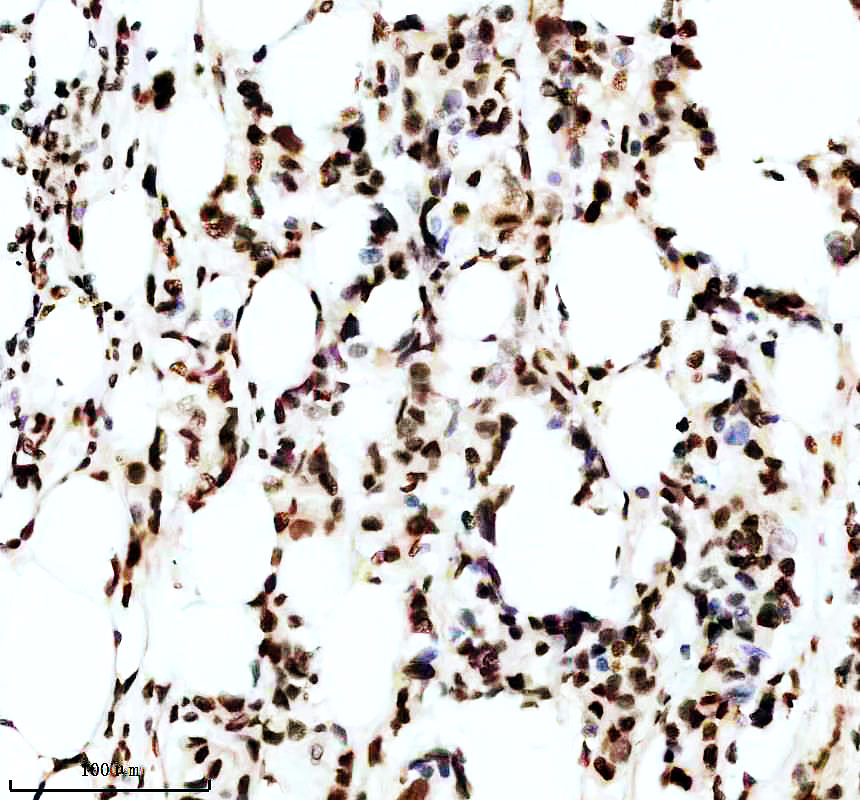

IHC analysis of P-MDM2 using anti-P-MDM2 antibody (P00054-2).

P-MDM2 was detected in a paraffin-embedded section of human lung cancer tissue. The tissue section was incubated with rabbit anti-P-MDM2 Antibody (P00054-2) at a dilution of 1:200 and developed using HRP Conjugated Rabbit IgG Super Vision Assay Kit (Catalog # SV0002) with DAB (Catalog # AR1027) as the chromogen.